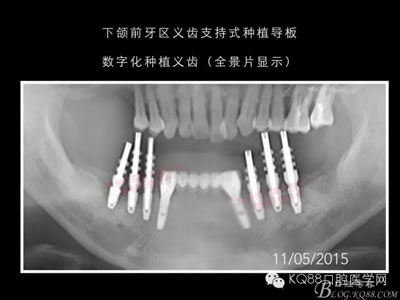

下面的種植病例是為患者提供全口牙齒治療修復完整過程的下頜部分,我們門診和患者共同配合下目前取得了較好的修復效果,即將開始的上頜牙齒治療修復過程仍然艱辛。